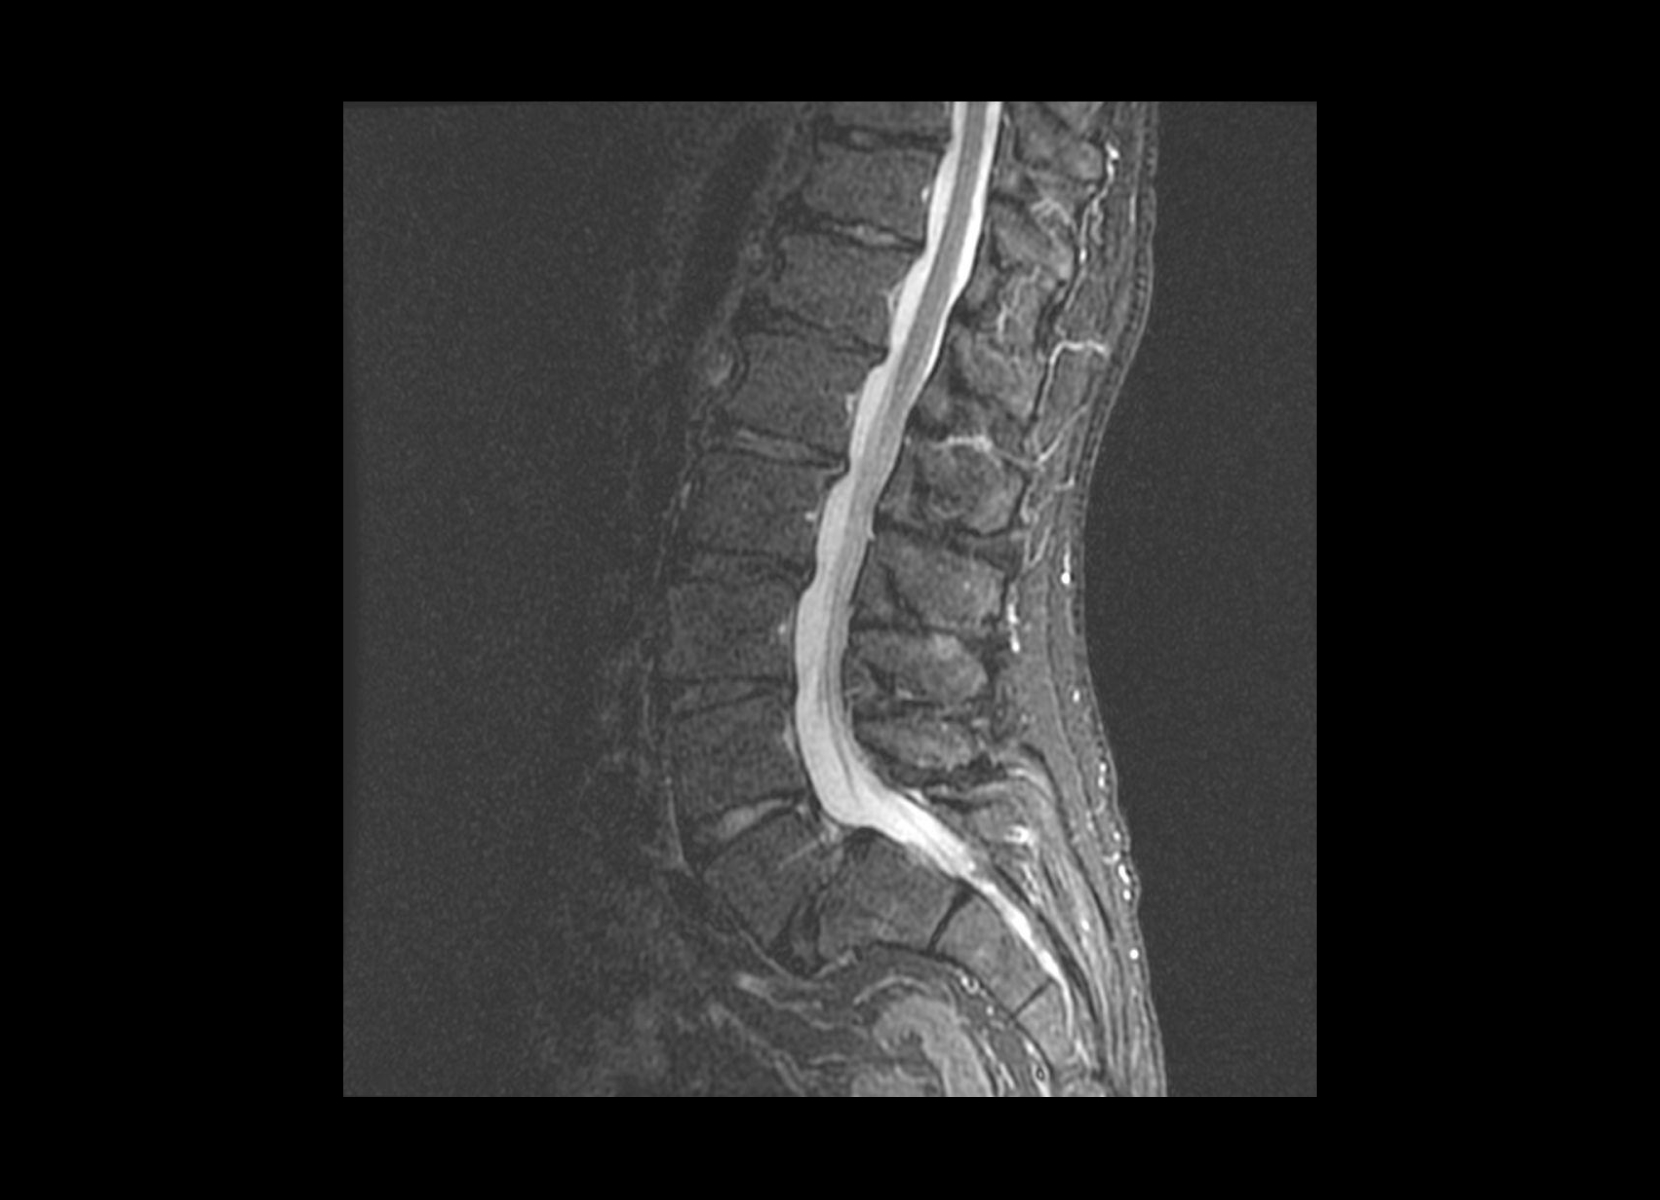

Conventional

STIR

SubtleSYNTH™

(Synthesized STIR)™

Cord lesion

GE 1.5T

C-spine